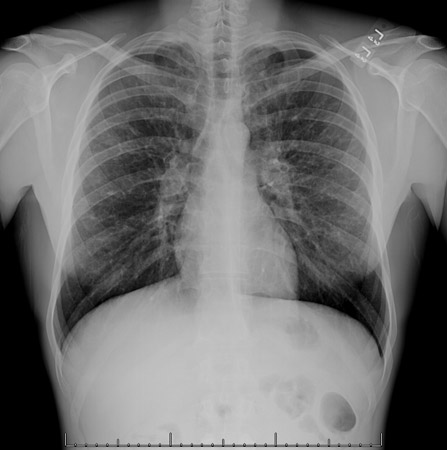

Chest x-ray showing bilateral hilar adenopathy in a patient with sarcoidosis

From the personal collection of Dr M.P. Muthiah, Division of Pulmonary and Critical Care and Sleep Medicine, University of Tennessee